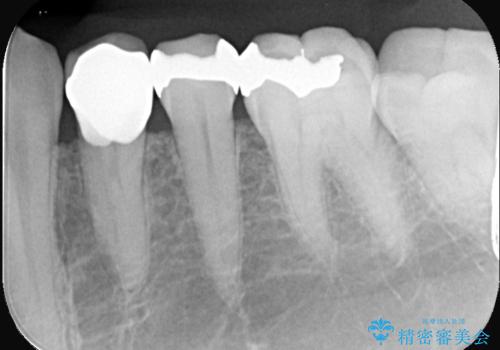

銀歯の下に虫歯 〈オールセラミッククラウン〉

- 初診時に金属の下に虫歯があることを指摘しました。もともとの詰め物の形と虫歯の大きさから被せものでの治療となりました。見た目、材質の説明をし、セラミッククラウンでの修復となりました。

メタルインレーが入っていたこと、う蝕が大きかったこと、頬側にHysに対してのCRがあったことを踏まえてクラウンでの修復を選択しました。